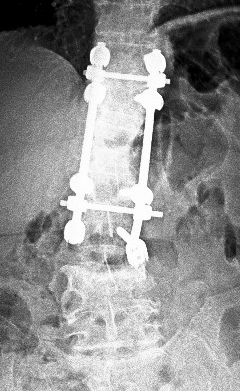

Hastaya lokal anestezi ve sedasyon altında sol unipediküler yolla vertebroplasti yapıldı (6 ml metilmetakrilat). Ayrıca faset medial dal blokları ve sol L3-4 ve L4-5 transforaminal epidural enjeksiyon da uygulandı.

L4 vertebroplasti sonrası kontrol grafileri

Resim 4: L4 vertebroplasti sonrası direkt grafiler.

Hasta işlemden sonra bel ve bacak ağrısında belirgin bir azalma (3-4/10) tarif etti. Kısa dönem takipte mobilizedir ve bir sorunu yoktur.